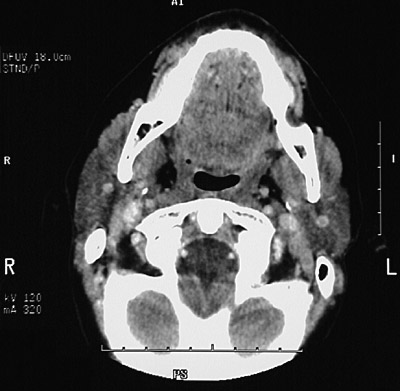

This is a normal axial head and neck CT scan demonstrating the mandible and oropharynx and facial vein and parotid gland and mastoid process and foramen magnum and vertebral artery and dens and C1 and internal jugular vein and internal carotid artery.